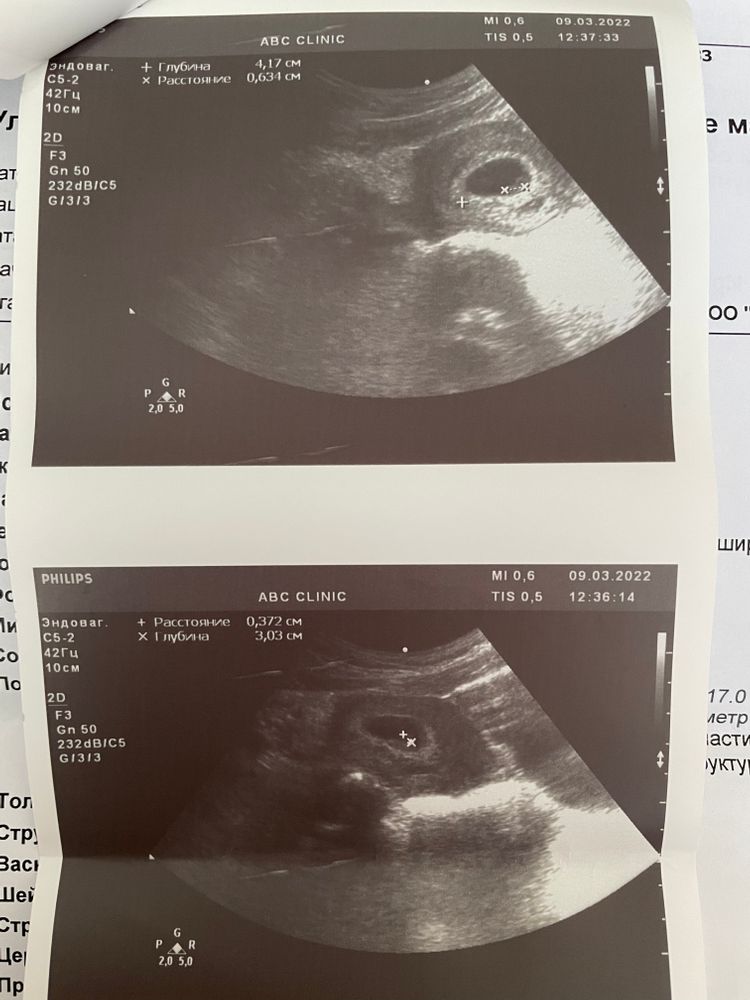

Первое УЗИ, 6н3д

по узи поставили мне 6,2 срок

ПЯ 17 мм

КТР 6,2 мм

ЖМ 3,7 мм

Эндометрий 28,5 мм

ЖТ 20 мм

Сердце стучит 🤍

Сказала, что все супер, небольшая гематома регрессирующая, которая ее не смущает, но порекомендовала половой покой пока придержать и через 2-3 недели вставать на учет 😌